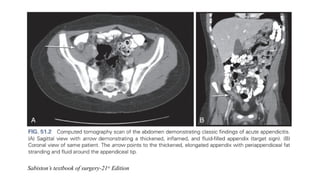

CT-scan

• A contrast-enhanced CT scan has a sensitivity of 0.96 (95% confidence interval

[CI] 0.95–0.97) and specificity of 0.96 (95% CI 0.93–0.97)

• Features on a CT scan that suggest appendicitis include

Enlarged lumen and double wall thickness

Wall thickening (greater than 2 mm)

Periappendiceal fat stranding

Appendiceal wall thickening and/or

An appendicolith

Sabiston’s textbook of surgery-21st

Edition